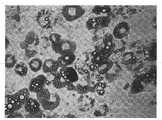

FIG. 1 shows a microscope image of adherent culture of placental and umbilical cord stem cells used in the present invention;

(3) And (3) culturing the placental stem cells by using a serum-free culture medium. CD140a positive cells (placental stem cells) were suspended in MesenGro serum-free medium, plated on Corning CellBIND cell culture dishes at 37 ℃ and 5% CO2Culturing in incubator, changing culture solution every 2-3 days, and digesting with trypsin for passage when cell density reaches 70-80% saturation. The morphology of the cells cultured in the MesenGro serum-free medium was similar to that of the cells cultured in the serum-containing medium (FIG. 1).